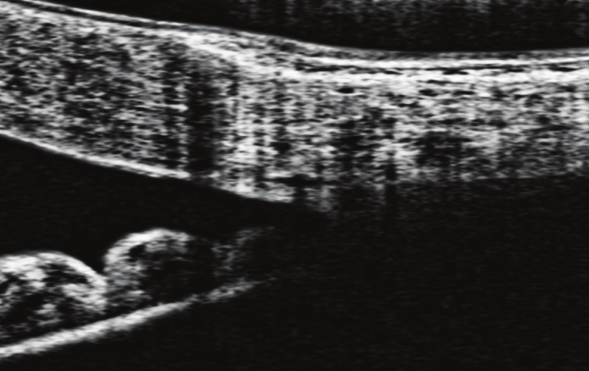

• A high-accuracy and high-efficiency digital volume correlation method to characterize in-vivo optic nerve head biomechanics from optical coherence tomography

• F Zhong, B Wang, J Wei, Y Hua, B Wang, J Reynaud, B Fortune, IA Sigal

image

• Acta Biomaterialia, 2022;143:72-86. April 2022, doi:10.1016/j.actbio.2022.02.021. PMID 35196556.